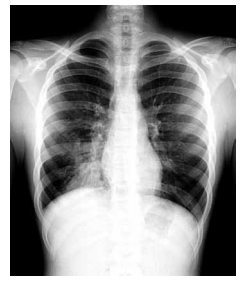

Mulher, 32 anos, refere que foi madrinha em um casamento há 3 dias e que dançou a noite inteira na festa. Após 48 horas, passou a apresentar dor muscular, febre de até 38ºC e dor ventilatório-dependente em hemitórax D. Nega uso de medicamentos nos últimos seis meses. Exame físico: paciente febril, 37,9 ºC, em bom estado geral; FC = 92 bpm; FR = 18 ipm; SpO2 em ar ambiente = 96%; PA 100 x 60 mmHg; ausculta cardíaca normal; ausculta pulmonar presença de estertores subcrepitantes em base pulmonar D. Foi realizada radiografia de tórax que está ilustrada a seguir.

Assinale a alternativa com a opção terapêutica correta.